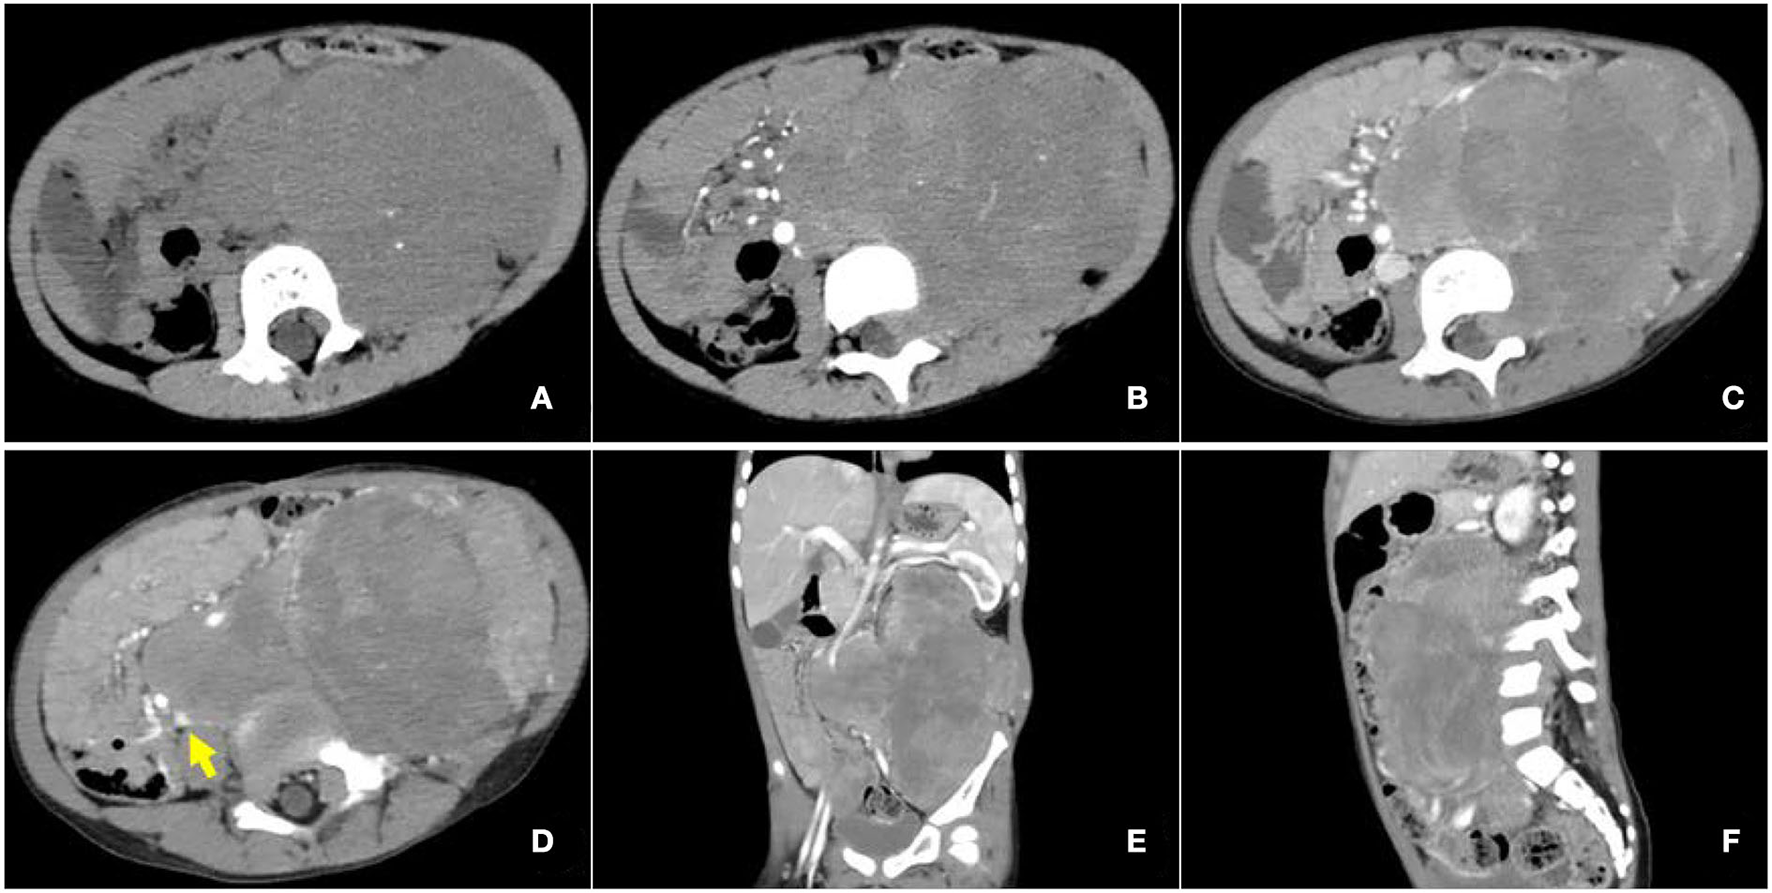

Contrast-enhanced CT examination indicated a huge soft tissue mass, measuring 12.3 × 7.4 cm at the larger section, in the left retroperitoneum extending superiorly to the level of the left hilus renalis and inferiorly to the left acetabulum in the pelvic cavity, with intrusion into the lumbar foramens, compression and squeezing of the left kidney and left abdominal bowel, local compression and stenosis of the inferior vena cava, and the abdominal aorta was displaced to the right side by compression (Figure 2). The tissue mass showed mottling calcification, cystic degeneration, and necrosis. The patient was injected with 0.1 mCi/kg of 18F-FDG after 6 h of fasting, and PET/CT images were acquired 60 min later. The tissue mass with a high FDG uptake was found using 18F-FDG PET/CT in the left retroperitoneum from the level of T12 to the left acetabulum, with the maximum standardized uptake value (SUVmax) of about 7.0 and a CT value of about 39 HU. The tumor invaded the left L3-5 intervertebral foramina and protruded into the spinal canal, with an unclear boundary with the spinal cord (Figure 3). The abdominal cavity and retroperitoneum showed enlarged lymph nodes, with a SUVmax of about 6.4 and the largest size of about 2.0 × 3.0 cm. No obvious abnormal FDG uptake was observed in the lung and bone.

Figure 2

Enhanced computed tomography (CT) images of retroperitoneal ARMS. (A) A plain image with a CT attenuation value of about 47 HU; mottling calcification existing within the mass; (B) Arterial phase image with a CT attenuation value of about 50 HU; the mass supplied by branches of superior and inferior mesenteric arteries and areas of cystic degeneration and necrosis without enhancement existing within the mass; (C–F) venous phase image with a CT attenuation value of about 65 HU. Left renal vein reflux could be observed in the mass. The mass invaded the lumbar intervertebral foramen and compressed the left kidney, left abdominal bowel, and the inferior vena cava, and the abdominal aorta was also compressed and displaced to the right. The arrow illustrates the involvement of the inferior vena cava.

Medical imaging provides noninvasive methods which are essential for the evaluation of patients with ARMS. The sonographic feature of ARMS is substantive hypoechoic or complex-echoic mass. CDFI shows rich and disorderly color blood flow signals within the mass. It often appears as an equal or a slightly low-density mass in plain CT, with unclear borders. The tumors usually grow rapidly, and necrosis, as well as cystic degeneration, can be seen in the lesions as a result of the insufficient blood supply. Enhanced CT scan shows heterogeneous enhancement and sometimes rim-like enhancement. Areas without enhancement are tissues with necrosis and cystic degeneration. Hemorrhage and calcification occur rarely, but mottling calcification was observed in this case. Moreover, CT can detect adjacent bone involvement but ARMS frequently destroy the bone. PET/CT reveals increased glucose metabolism of ARMS. As an advanced technology, PET/CT could provide more information about the lesions than conventional imaging detection methods. 18F-FDG PET/CT imaging is useful for initial assessment, monitoring treatment response, and detection of recurrences with better accuracy for identifying primary sites, lymphatic involvement, and distant metastases (22, 23). Local lymph node metastasis has been considered a strong prognostic factor, calling for an emphasis on desirable detection modalities of lymphatic involvement (24). Compared with conventional imaging techniques, such as ultrasound, CT, and magnetic resonance imaging (MRI), PET/CT performs better in detecting lymph nodal metastasis with higher sensitivity and specificity (25). 18F-FDG PET/CT can estimate the function and nature of nodes through the level of glucose metabolism in tissues and can help with accurate localization of the involved lymph nodes. In a prospective study by Völker et al. (25), the detection of involved lymph nodes using 18F-FDG PET/CT reached a sensitivity of 93%, whereas conventional imaging modalities were only 36%. Ricard et al. (26) reported that 18F-FDG PET/CT found 19 involved lymph nodes in 4 patients vs. 12 nodes by MRI and CT, and therefore, the results of PET/CT led to alteration of the lymph node staging and treatment strategies in some patients. Our case also observed similar advantages of PET/CT for discovering retroperitoneal lymphatic metastases, whereas negative in ultrasound and CT tests. The more accurate staging of regional lymph node involvement will benefit risk stratification and treatment decisions in patients with RMS. PET/CT also shows some potential superiorities in finding tumor invasion into the spinal canal. When evaluating the spinal canal involvement, all background tissues, including paraspinal musculature, vertebrae, spinal cord, nerve roots, and CSF, demonstrate relatively low metabolic activity using 18F-FDG PET/CT, thus making it possible for differentiation between normal tissues and lesions (27, 28). PET/CT allows for the identification of soft-tissue involvement such as neural foramen invasion and epidural extension of tumor in malignant involvement of the spine (29). However, PET/CT is inferior to MRI when used to detect spinal cord involvement. In recent years, the integrated PET and MR (PET/MR) imaging modality has been rapidly developed with the combined superiorities of quantification of radioactive tracer metabolism provided by PET and outstanding soft tissue contrast by MR (30). The value of PET/MR in clinical applications remains to be established, and we hope this innovative technology will provide more accurate diagnosis and ultimately improve patient prognosis. In addition, a study illustrated that metabolic parameters obtained from baseline PET/CT were potential to select patients sensitive to treatment (31). Features of patients including unfavorable sites of the primary tumor, older patient age at initial presentation, the alveolar subtype, and regional lymph node involvement are considered to be poor prognostic factors for RMS (5, 32). Unfavorable sites include the prostate and bladder, cranial parameningeal sites, extremities, trunk, retroperitoneum, and other sites (13). Moreover, 18F-FDG PET/CT may be an added prognostic predictor in RMS. High SUVmax value is more prevalent among patients with less favorable features including unfavorable primary sites, alveolar pathology, and high-risk group (33). A study found that during diagnosis, patients with SUVmax of <9 had an improved 3-year progression-free survival (62% of patients with SUVmax of <9 vs. 39% of patients with SUVmax of ≥9, p = 0.02) (34). In our case study, the SUVmax of 7.0 might be associated with the patient's favorable prognosis.